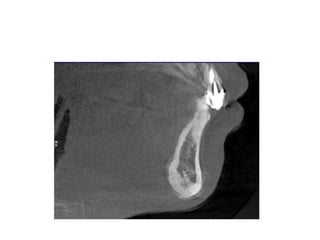

Enlarged adenoids

• Enlarged adenoids correlated with the open

mouth position.(AJR Am J Roentgenol. 2002

Aug;179(2):503-8 )

• The nasopharynx and hypopharynx changes only

minimally with respiration any motion greater

than 5 mm should be considered abnormal.

• Adenoid enlargement most likely does play a role

in the development of obstruction in obstructive

sleep apnea.